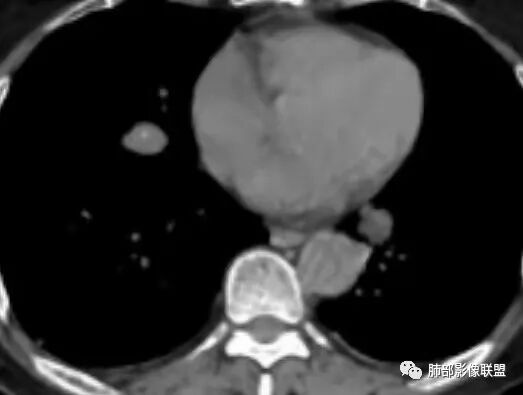

2.右髂骨轻度变形伴广泛骨质吸收破坏,边界不清且突破骨皮质。近中线区以溶骨性破坏为主,髂骨翼一侧则成骨性改变明显,骨表面见垂直骨针或花边样高密度瘤骨。

3.患骨多处皮质断裂,符合病理性骨折。注意折端可能会形成骨痂,但本例无论是形态还是部位都不符合骨痂。

4.患骨两旁(即盆骨内外)见边界不清的较大范围软组织快影,其间偶见骨化影。

5.双肺多发类圆形结节影,边界清楚,随机分布,其间多见钙化密度影。

本例右侧髂骨具有较为典型的“骨肉瘤”影像学特征,有边界不清的吸收破坏、有新生骨、形成软组织肿块等等。

3.双肺病灶符合转移瘤,伴有中央部分钙化者也以骨肉瘤转移较为多见。

4.“成骨肉瘤”绝大多数发生于青少年,发生于老年患者则往往见于其他因素,如诱发于畸形性骨炎(Paget病,本例影像不支持),骨照射、骨坏死等。其他如骨旁骨肉瘤等,发病年龄可以偏大。